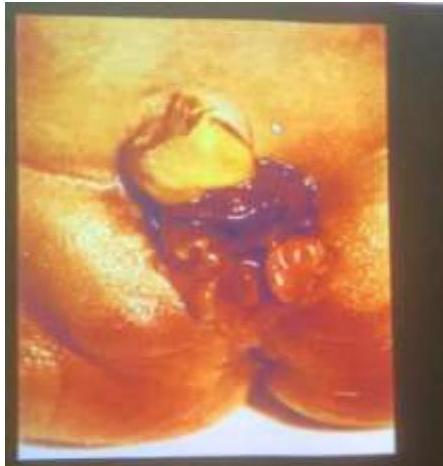

Intussusception

- 18 Months old boy presented with crying and vomiting.

- A bloody stool was passed on the day of the imaging examinations.

Diagnosis? Ileocolic intussusception.

Investigation? Barium enema.

Sign?

- Cut-off sign in the middle

- Coiled spring appearance / spring sign

Etiology:

- Idiopathic

- Secondary to: HSP, intestinal polyps

Emergency:

- Type of obstruction

Treatment:

- NPO/IV fluids

- NGT aspiration

- IV antibiotics

- Hydrostatic reduction with Barium/air enema

- Laparotomy and resection if needed

Complications:

- Ischemia and necrosis